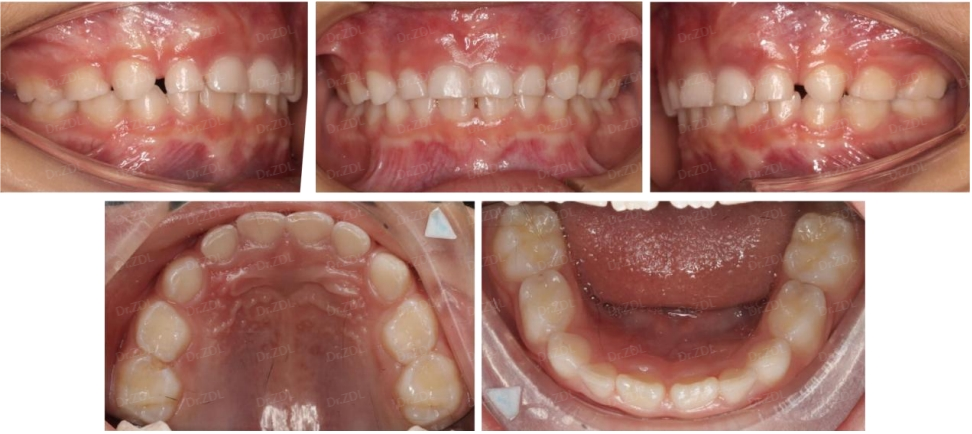

Grace硅胶牙套案例1:

像这位8岁小朋友主诉门牙有缝、牙不齐、嘴凸,家长也比较重视孩子的口腔健康和颌面发育问题。根据牙片资料和口内检查发现,孩子恒牙胚数量无缺失,牙根发育正常,骨性I类,均角面型,生长方向正常,上前牙唇倾不齐,上颌稍前突,下颌稍后缩。

根据孩子牙齿情况,采用Grace轨道式硅胶矫治器,恢复上下颌正常牙弓宽度,匹配上下颌牙弓形态,引导上下恒牙正常萌出,引导下颌前伸,并日常辅助唇肌功能训练。

Grace佩戴6个月,上颌中切牙间隙完全关闭,牙弓形态调整良好,下前牙萌出排齐良好。